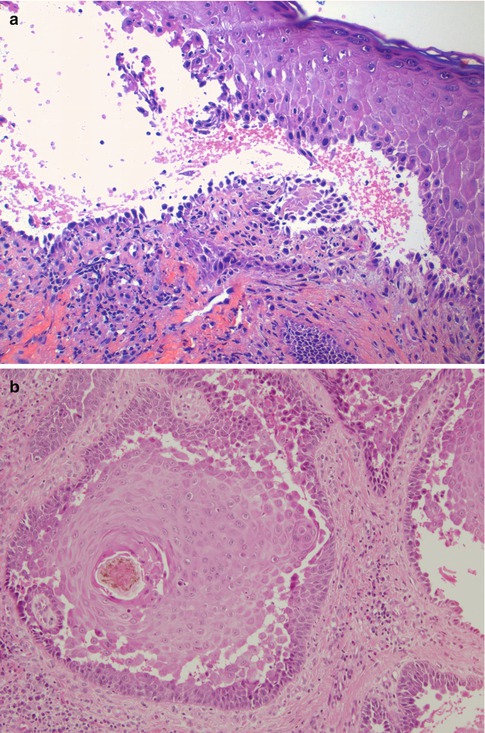

Fig. 16.2

(a) Pemphigus vulgaris. Intraepidermal blister located suprabasally with acantholytic cells floating inside the vesicle. The cells of the basal layer remain attached to the basement membrane zone showing a characteristic row of tombstone pattern (hematoxylin-eosin stain; original magnification ×200). (b) Pemphigus vegetans. Acanthosis and pseudoepitheliomatous hyperplasia together with suprabasal clefting and prominent acantholysis (hematoxylin-eosin stain; original magnification ×100). (c) Pemphigus foliaceus. Intraepidermal blister located within the stratum corneum (subcorneal) with some acantholytic cells floating inside the vesicle (hematoxylin-eosin stain; original magnification ×200). (d) Pemphigus foliaceus. There is no evident intraepidermal blister. The clues for diagnosis are the absence of stratum corneum and granulosum and the presence of neutrophilic spongiosis (epidermal spongiosis with presence of neutrophils) (hematoxylin-eosin stain; original magnification ×200). (e) Paraneoplastic pemphigus. There is no acantholysis. The biopsy shows a prominent lichenoid dermatitis with several necrotic keratinocytes and basement membrane vacuolization. This patient had an associated follicle center lymphoma (hematoxylin-eosin stain; original magnification ×200). (f) IgA pemphigus of the subcorneal pustular dermatosis subtype. Subcorneal pustule with abundant neutrophils and superficial epidermal spongiosis (hematoxylin-eosin stain; original magnification ×40)

The initial histological finding in pemphigus vulgaris (PV) is the appearance of intercellular edema between keratinocytes that ultimately leads to a separation between cells and rupture of the spinous processes leading to a phenomenon that we call acantholysis. In PV this process takes place characteristically in the suprabasal layer, producing suprabasal intraepidermal blisters, and there may be cells floating inside the vesicle, the so-called acantholytic cells. These cells are round, with a hyperchromatic nucleus and homogeneous cytoplasm. The cells of the basal layer remain attached to the basement membrane zone (BMZ) by their hemidesmosomal attachments and produce a characteristic image that has been compared to a row of tombstones (Fig. 16.2a) [1]. In the underlying dermis there are usually mild to scarce perivascular inflammatory infiltrates of mononuclear cells and some eosinophils. In some cases the epidermal changes are absent, and acantholysis can only be seen in the follicular epithelium selectively, without affecting the interfollicular epidermis [2]. In some patients, before blistering occurs the patients present with inflammatory plaques that show histologically a spongiotic dermatitis with abundant eosinophils within the epidermis, a histological pattern that has been referred to as eosinophilic spongiosis [3]. Although this finding was initially described in pemphigus (both vulgaris and foliaceus), it can be seen in other autoimmune bullous diseases and in other disorders. In fact, eosinophilic spongiosis is much more frequently seen in the pre-bullous stages of bullous pemphigoid than in pemphigus.

The findings in pemphigus vegetans (PVeg) show some characteristics that are different from those of PV. Although early lesions may show suprabasal acantholysis, as in PV, fully developed lesions of PVeg will show acanthosis and papillomatosis, sometimes with prominent pseudoepitheliomatous hyperplasia, and the presence of intraepidermal abscesses of eosinophils. Suprabasal acantholysis may be very subtle and therefore may be missed in some cases (Fig. 16.2b) [4]. The differential diagnosis has to be done with conditions like pyostomatitis vegetans, Hailey-Hailey disease, or blastomycosis-like pyoderma (also known as pyoderma vegetans). Classically, PVeg can be divided in two subtypes, the Neumann and the Hallopeau subtype, that differ clinically and histologically. In the Neumann subtype, lesions are characterized by papillomatosis and acanthosis with intraepidermal vesiculation and suprabasal acantholysis. Intraepidermal pustules of neutrophils and eosinophils are scant or absent. In the Hallopeau subtype, lesions will also demonstrate acanthosis with occasional acantholysis, but with numerous and large eosinophilic abscesses, as well as areas of eosinophilic spongiosis. In late lesions the histological findings will overlap in both subtypes.

The histopathological findings in endemic and non-endemic pemphigus foliaceus (PF), pemphigus erythematosus, and drug-induced cases of pemphigus are identical. They are characterized by the presence of superficial acantholysis, just below the granular layer of the epidermis (Fig. 16.2c). Initial vesicles can contain abundant neutrophils or eosinophils. Occasionally, as a result of the blisters having a very thin ceiling, they break and loose the upper layer. This may give the appearance of a “normal epidermis” or even of a psoriasiform dermatitis, with no clear finding of acantholysis. The clue for diagnosis in these cases is the absence of stratum corneum and parts of the stratum granulosum (Fig. 16.2d) [5]. The main differential diagnosis here is with impetigo and staphylococcal scalded skin syndrome that are both disorders caused by the cleavage of the extracellular domain of desmoglein 1 by a toxin produced by certain strains of Staphylococcus aureus.

16.1.1.3 Paraneoplastic Pemphigus

The classic pattern described in paraneoplastic pemphigus (PNP) is the presence of intraepidermal blisters with suprabasal acantholysis (similar to PV), combined with lichenoid changes including interphase dermatitis, presence of necrotic keratinocytes and lichenoid inflammatory infiltrates [8]. These histological findings are not completely specific of PNP and they have also been found in erythema multiforme, toxic epidermal necrolysis, and approximately one third of cases with other forms of pemphigus [9]. In the personal experience of the author, the classic pattern of PNP can be observed in only 20 % of the biopsies from these patients, while 50 % of the biopsies showed a histological pattern indistinguishable from PV (intraepidermal blisters with suprabasal acantholysis), and 30 % of the biopsies showed only purely lichenoid changes without acantholysis (Fig. 16.2e). Sometimes we can observe the combination of the different patterns in different biopsies (i.e., one biopsy showing suprabasal acantholysis and another a lichenoid pattern). Eosinophilic spongiosis has also been reported in PNP [10].

16.1.1.4 IgA Pemphigus

There are two major clinicopathological subtypes of IgA pemphigus (IAP). In the subcorneal pustular dermatosis subtype of IAP, histological examination of the lesions shows epidermal spongiosis with exocytosis of neutrophils and some eosinophils and the formation of subcorneal collections of neutrophils (Fig. 16.2f). Acantholysis is usually not seen, and if it is present, there are usually only isolated cells. In the superficial dermis there are perivascular infiltrates of neutrophils, eosinophils, and lymphocytes [11]. The differential diagnosis in this subtype of IAP must be made with subcorneal pustular dermatosis of Sneddon-Wilkinson, pustular psoriasis, acute generalized exanthematous pustulosis, or impetigo. The intraepidermal neutrophilic dermatosis subtype of IAP shows epidermal acanthosis with spongiosis and exocytosis of neutrophils and eosinophils. These cells tend to form microabscesses and pustules inside the stratum spinosum of the epidermis. In the dermis there is papillary edema and perivascular infiltrates with abundant neutrophils, eosinophils, and lymphocytes. Acantholysis is also very rare in the biopsies of these patients, although some cases have been reported where there were suprabasal blisters identical to those of PV [12, 13]. The differential diagnosis in this subtype of IAP has to be done with pemphigus vegetans (Hallopeau type) and halogenodermas. Patients with IAP with features of PV or PF have also rarely been reported, and they were histologically identical to conventional PV or PF.